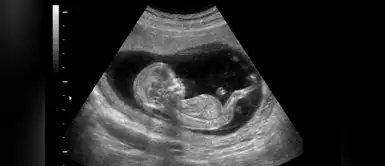

Eso podría explicar la sorpresa que este bebé les dio a sus padres. La mujer junto a su esposo se estaba sometiendo a una ecografía a las 28 semanas cuando al parecer el feto los estaba saludando, la pareja no podía creer lo que estaba pasando.

En el clip se aprecia en un momento el feto girando hacia la “cámara” y empieza a agitar una de sus manitas como si estuviera saludando a sus papás. El doctor quedó impresionado ante las imágenes ya que él comenta que nunca le había pasado eso.